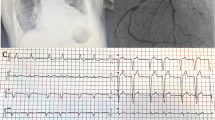

CA usually has basal–apical distribution of late enhancement while apical segments are frequently spared. LGE occurs in up to 40% of isolated AS cases, being present primarily in the LV with a focal mesocardiac pattern but with possible involvement of the right ventricle and atrial myocardium [20]. Different LGE patterns correlate with different etiologies. TTR-CA follows a basal–apical enhancement distribution where apex can be spared and a higher presence of RV involvement. On the contrary, AL–CA has a circumferential subendocardial involvement that can extend to transmural pattern (Fig. 1) [21].

In amyloidosis, T1 relaxation time values are typically increased as a result of the extracellular deposition of the amyloid protein. The T1 mapping (A) displays on a color scale the T1 values of the myocard, blood, and surrounding structures. On the polar map, (B) a diffuse increase of the T1 values is reported (in this case normal values < 1250 ms on a 3 T CMR). The resulting ECV values (normal values < 30%) are consequently also increased (C, D)